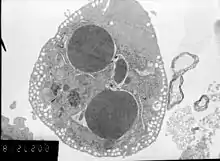

A cell undergoing apoptosis shows a series of characteristic morphological changes. Early alterations include:

- Cell shrinkage and rounding occur because of the retraction lamellipodia and the breakdown of the proteinaceous cytoskeleton by caspases.[53]

- The cytoplasm appears dense, and the organelles appear tightly packed.

- Chromatin undergoes condensation into compact patches against the nuclear envelope (also known as the perinuclear envelope) in a process known as pyknosis, a hallmark of apoptosis.[54][55]

- The nuclear envelope becomes discontinuous and the DNA inside it is fragmented in a process referred to as karyorrhexis. The nucleus breaks into several discrete chromatin bodies or nucleosomal units due to the degradation of DNA.[56]

Apoptosis progresses quickly and its products are quickly removed, making it difficult to detect or visualize on classical histology sections. During karyorrhexis, endonuclease activation leaves short DNA fragments, regularly spaced in size. These give a characteristic "laddered" appearance on agar gel after electrophoresis.[57] Tests for DNA laddering differentiate apoptosis from ischemic or toxic cell death.[58]